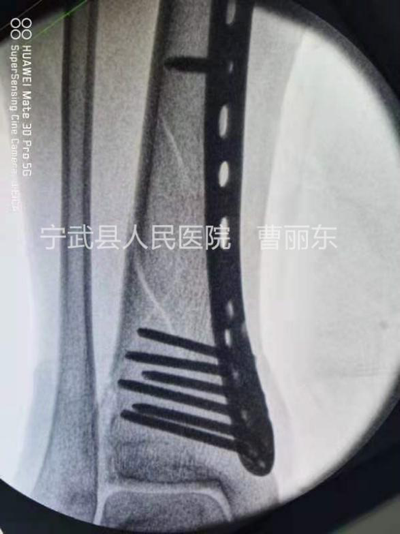

这是一例胫骨中下段螺旋形骨折,同样通过微创置入钢丝捆扎复位,置入钢板